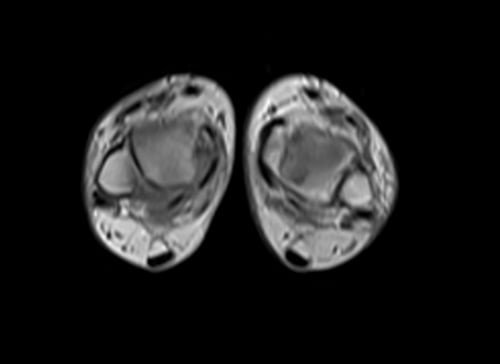

mri lower legs (calves) t1 axial image 3 - MRI